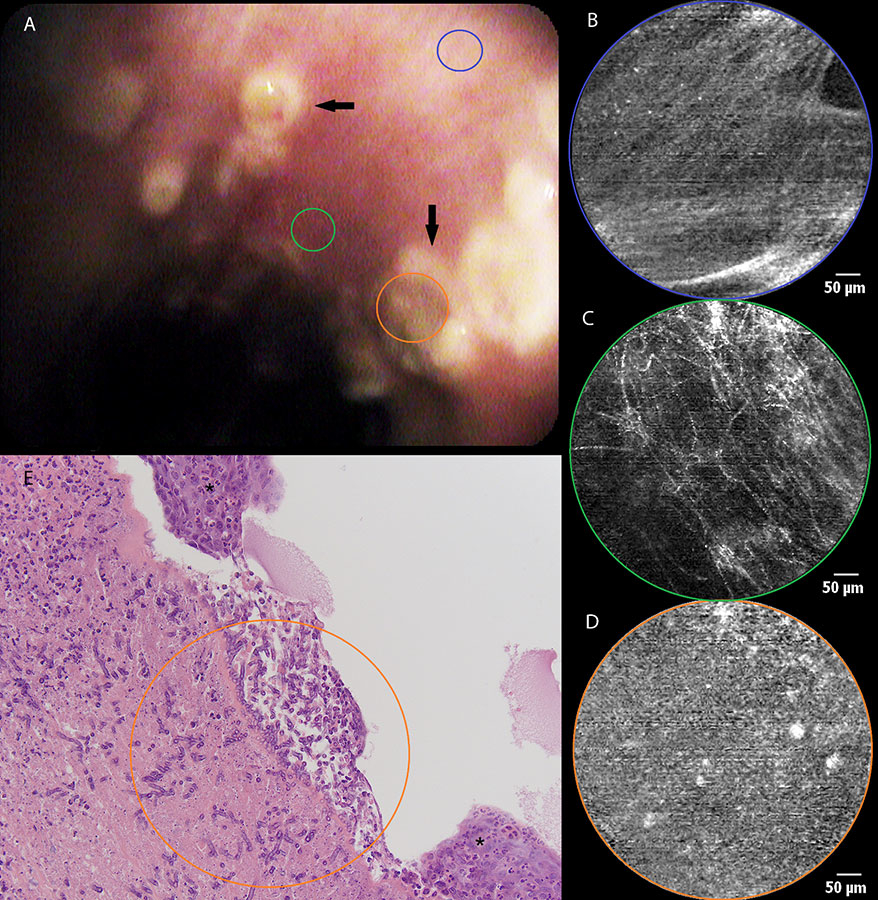

Figure 1

a) White light bronchoscopy and b) autofluorescence bronchoscopy showing mucosal abnormality (orange area) at the level of the main carina in a patient with haemoptysis. c) pCLE imaging of healthy bronchial mucosa (blue area) showing longitudinally arranged elastic fibres and the opening of a bronchial gland (asterisk). d) pCLE imaging of the main carina : partial disappearance of the longitudinal arrangement of elastic fibres, appearance of round opacities (20 µm in diameter) with intense autofluorescence. e) Histopathological specimen of a biopsy obtained from the main carina showing a squamous cell carcinoma: large and polygonal cells containing eosinophilic cytoplasm and showing intercellular bridging. Some necrosis and re-epithelisation are present.

A 66-year-old man with a medical history of a total laryngectomy for an invasive squamous cell carcinoma of the left vocal cord was referred for bronchoscopy because of recurrent haemoptysis. White light bronchoscopy was normal except for a small sclerotic lesion (5 mm in diameter) at the level of the main carina (fig. 1a). Autofluorescence bronchoscopy demonstrated a zone of low enhancement, corresponding to the location of the sclerotic lesion (fig. 1b). No other abnormalities were found throughout the tracheobronchial tree. pCLE imaging at the normal-looking part of the main carina showed a pattern of longitudinally arranged elastic fibres, known to be the normal appearance of bronchial mucosa in healthy volunteers (fig. 1c) (1). When bringing the confocal probe to the before-mentioned lesion, we noticed the local disappearance of this longitudinal arrangement of elastic fibres, demonstrating the disruption of the normal mucosal lining in this area. Some round hyperfluorescent opacities with a diameter of around 20 µm could be seen in this area, possibly corresponding to cellular structures (fig. 1d). At the end of the procedure, biopsies were taken, revealing the presence of a squamous cell carcinoma (fig. 1e). The lesion was treated with local laser coagulation and the patient was kept in endoscopic follow-up, showing no evidence of recurrence until now. Moreover, pCLE characteristics of the main carina returned to normal during follow-up bronchoscopy 6 months after diagnosis, despite a persisting reduction in autofluorescence intensity.

Our experience during the first eighty-eight procedures performed is reflected using these five illustrative cases. The main goal was to give a realistic overview of what the basic technique in pCLE imaging of the respiratory tract is capable of at this moment. As mentioned before, what determines the appearance of central airway mucosa is autofluorescence of elastic fibres. Not surprisingly, in the first two cases pCLE imaging shows the disruption of the normal mucosal lining due to two pathological conditions of the bronchial mucosa (e.g. squamous cell carcinoma and ulcerations due to tracheobronchial aspergillosis). When considering the histopathological specimens, one can easily understand that the layers of elastic fibres located underneath the basal membrane, are disrupted due to the localised ulceration. The pCLE images obtained show that the normal aspect of the bronchial wall is changed, but these images are quite similar in both conditions and can’t be said to be specific for one condition or another.